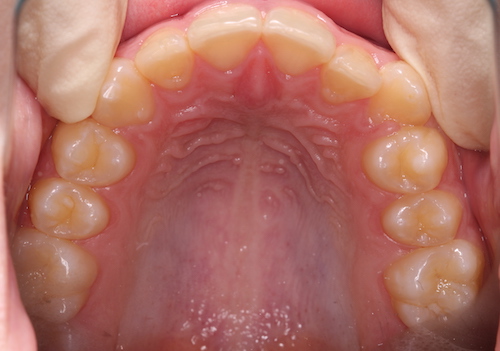

До